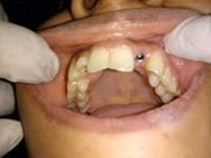

Placement of Abutement

Single Tooth Implant